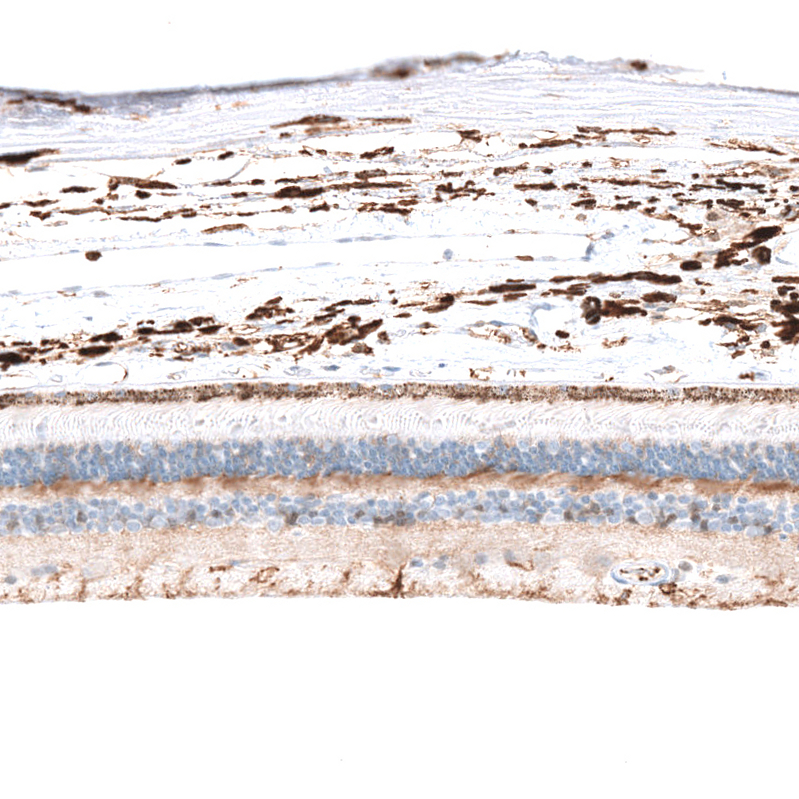

Immunohistochemical staining of human eye, retina shows moderate cytoplasmic positivity in outer nuclear layer and inner plexiform layer..